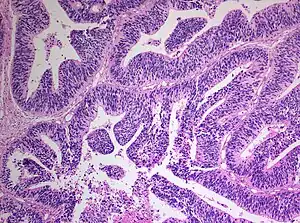

| Histopathology of medulloepithelioma showing characteristic neural tube like strands. | |

Histologically, medulloepithelioma resemble a primitive neural tube and with neuronal, glial and mesenchymal elements.[8][9] Flexner-Wintersteiner rosettes may also be observed.[10]

Immunohistochemically, neural tube-like structures are vimentin positive in the majority of medulloepitheliomas.[11] Poorly differentiated medulloepitheliomas are vimentin negative.